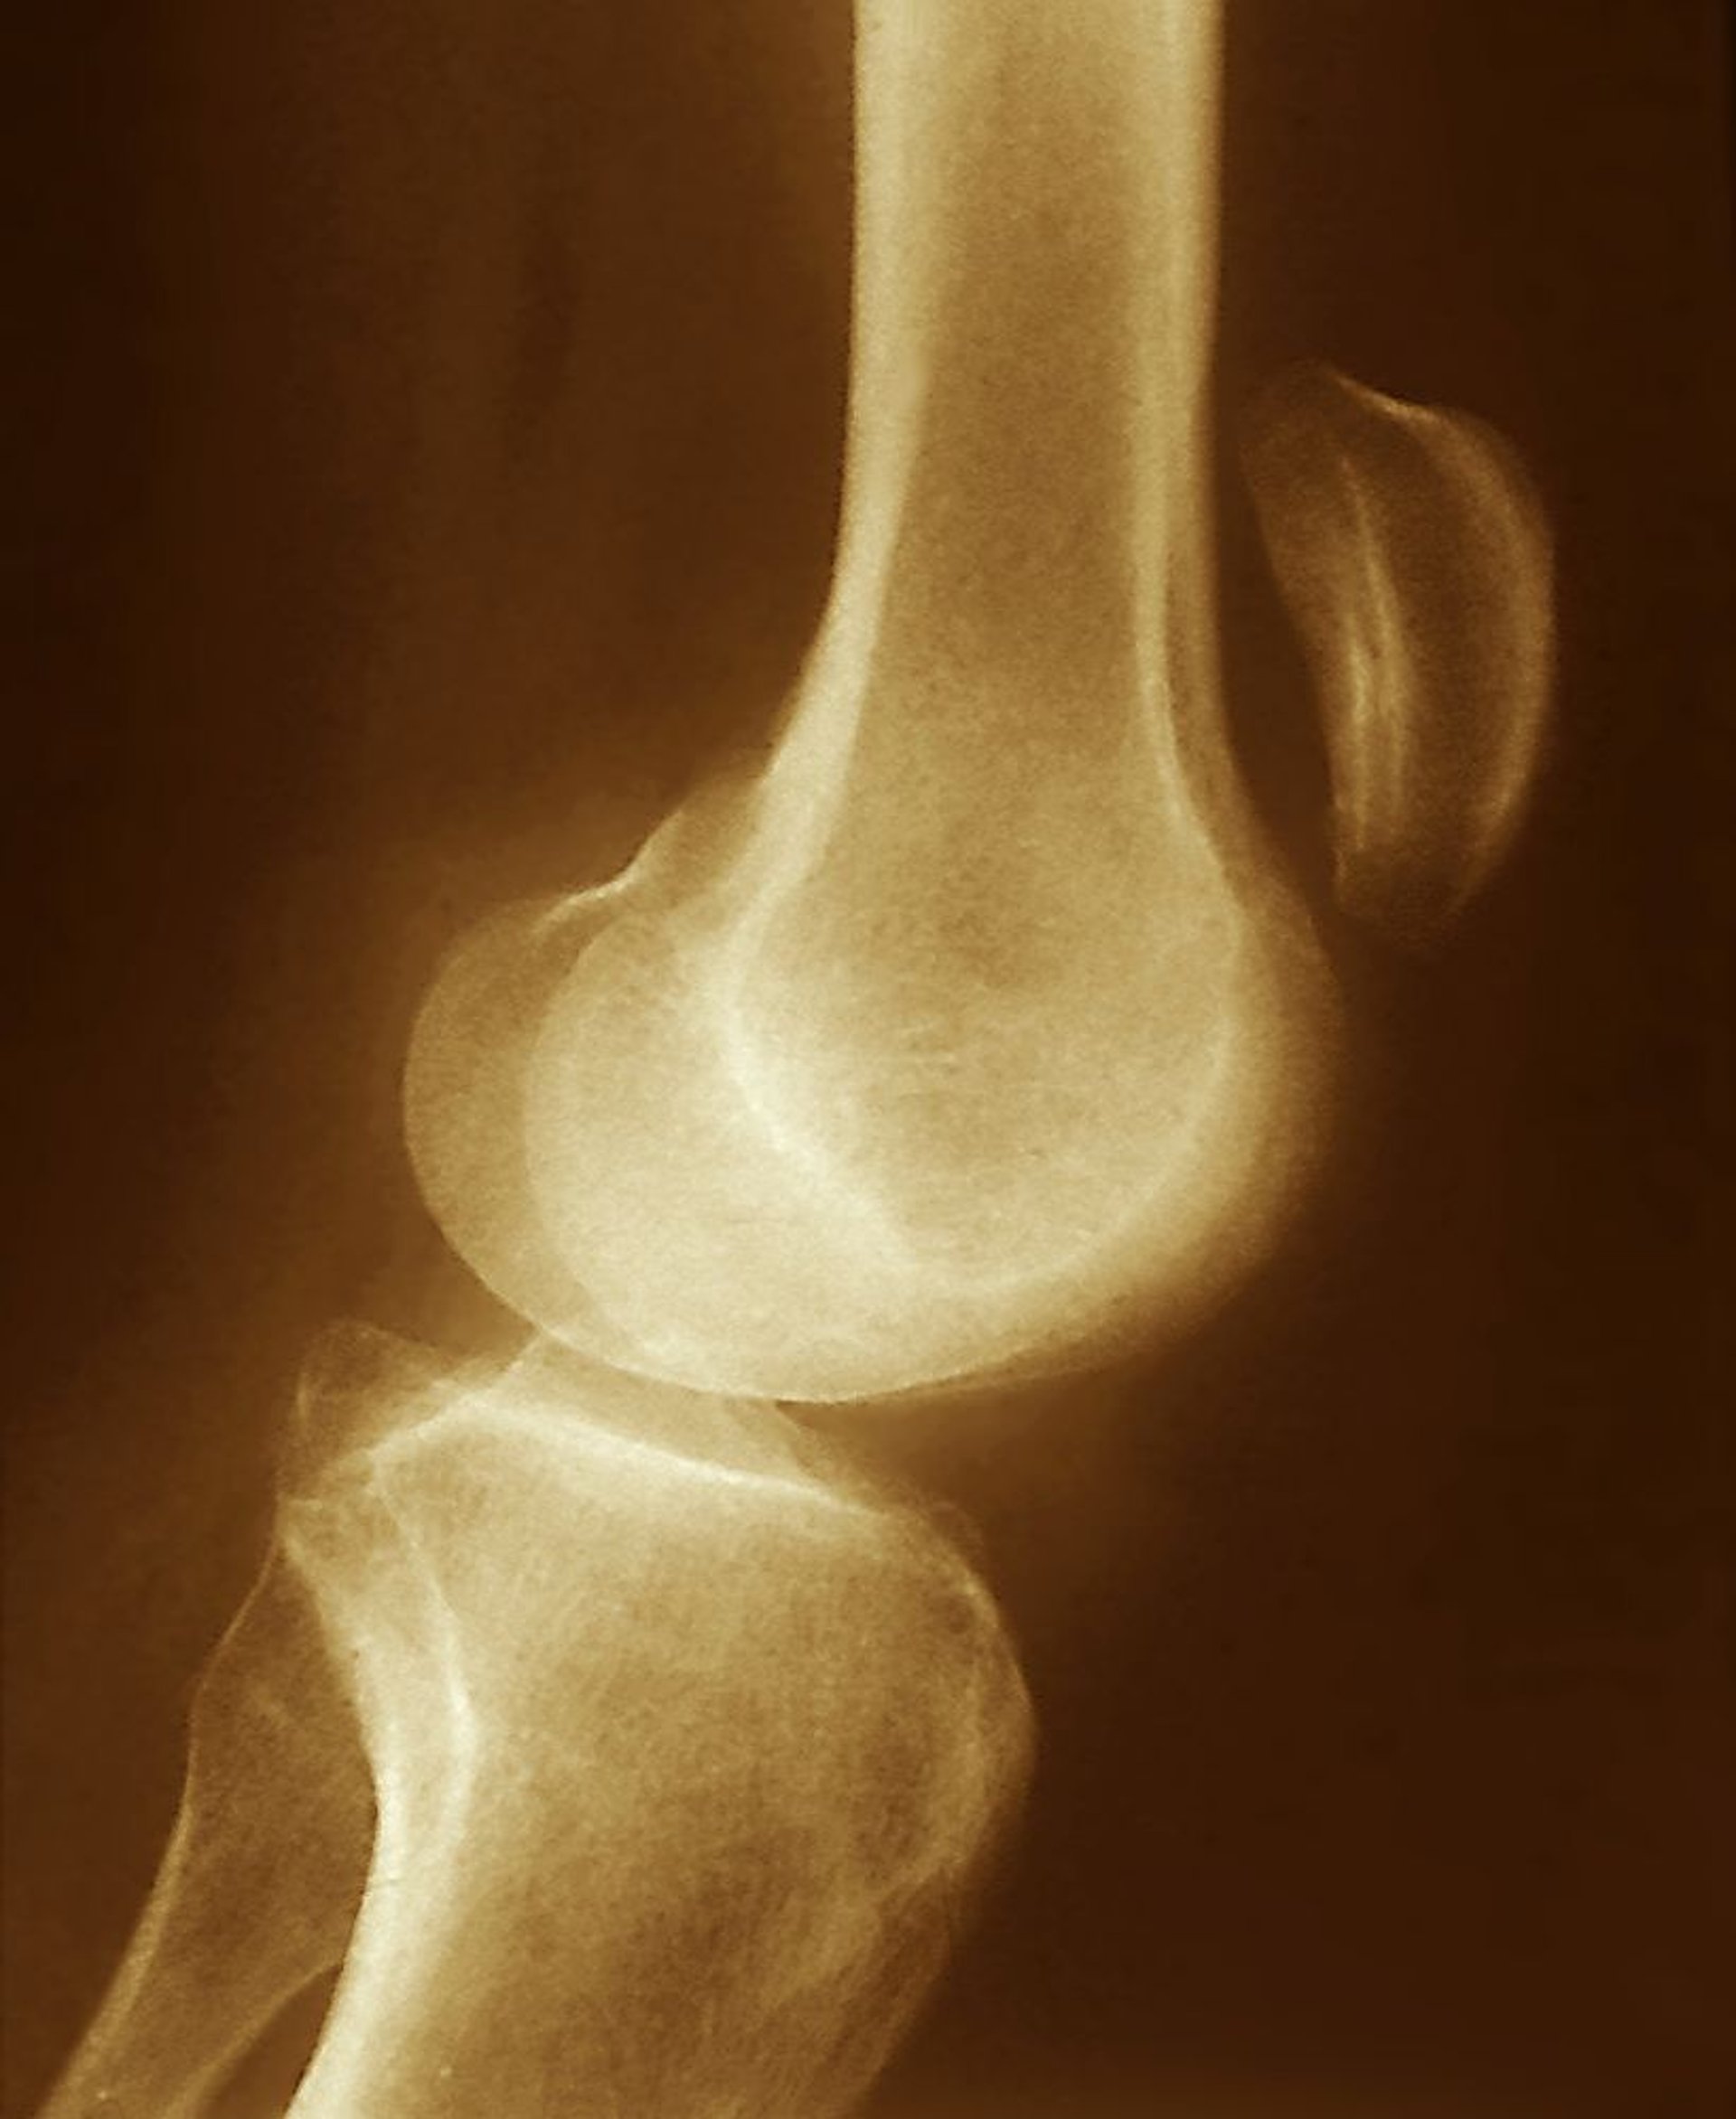

Déchirure du tendon rotulien

Le déplacement supérieur de la rotule observé sur cette radiographie (bien au-dessus de l'articulation du genou) suggère une déchirure du tendon rotulien, avec une contraction non opposée du quadriceps.

ZEPHYR/SCIENCE PHOTO LIBRARY